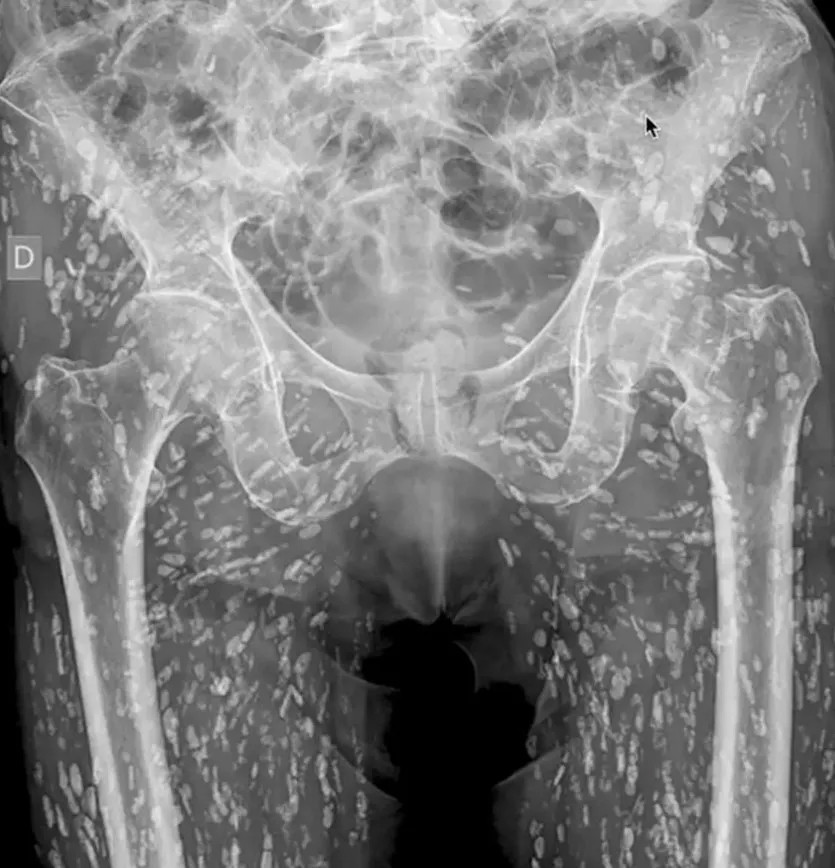

Bác sĩ người Mỹ Sam Ghali đã chia sẻ thông tin sức khỏe của người đàn ông giấu tên và nói rằng đó là "một trong những phim chụp X-quang đáng sợ nhất mà tôi từng thấy". Vị bác sĩ nói thêm: "Đây là các nang ấu trùng của sán dây taenia solium còn được gọi là sán dây lợn".

Tình trạng đó xảy ra khi một người ăn thịt lợn sống hoặc chưa nấu chín dẫn tới nhiễm sán trong đường tiêu hóa. Những nang này có thể di chuyển khắp cơ thể con người. Ở bệnh nhân trên, các nang ấu trùng đã di chuyển rất nhiều đến các mô cơ và mô mềm ở hông và chân.

Người đàn ông tình cờ phát hiện ra bệnh khi đi chụp X-quang do bị ngã và đau hông. Trong trường hợp này, các nang không gây ra vấn đề đe dọa tính mạng. Nhưng trong một số ca, nang ấu trùng có thể gây ra bất ổn nghiêm trọng, đặc biệt khi di chuyển tới não. Bệnh ấu trùng sán dây thần kinh có nguy cơ dẫn đến các triệu chứng như đau đầu, lú lẫn, co giật, thậm chí tử vong.